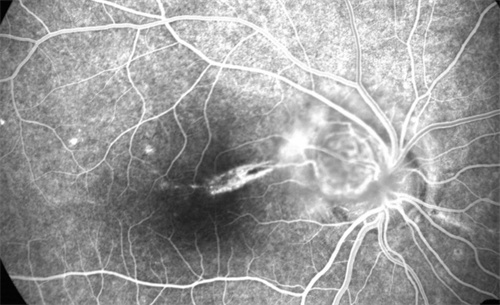

糖尿病视网膜病变,也被称为糖尿病性视网膜病变或糖网病。它是由于糖尿病导致视网膜微血管受损,进而影响视力。

随着病情的发展,患者可能出现视力下降、视物模糊、眼前黑影等症状,重度时甚至会导致失明,给患者的生活和工作带来极大不便。